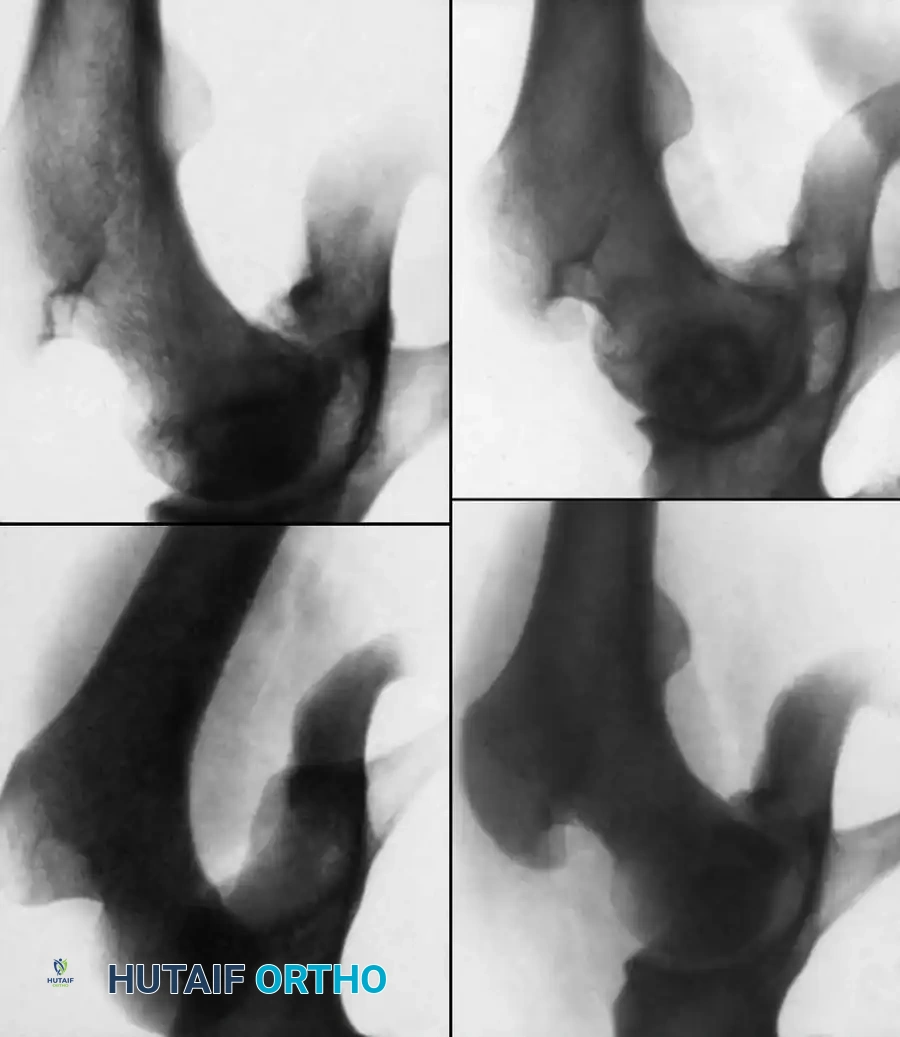

Fig. 33-125 Osteonecrosis of the femoral head after hip dislocation. A, Traumatic dislocation in an older child. B, After satisfactory closed reduction. C, At 1 year after reduction, suggestion of early osteonecrosis. D, At 8 years after reduction, cystic appearance of osteonecrosis.